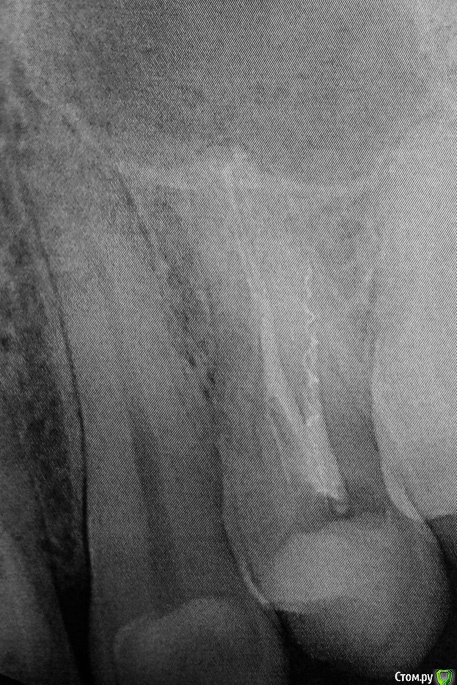

regi Опубликовано 24 февраля, 2016 Поделиться Опубликовано 24 февраля, 2016 (изменено) Сегодня мне начали лечение зуба. Пока только прошли каналы и поставили временную пломбу.В настоящий момент при надавливании на зуб чувствуется острая боль.Решил поизучать внимательно снимок и обнаружил внутри канала обломок. Врачу снимок еще не показывал (должен принести на следующий приём).На что следует обратить внимание при дальнейшем общении с врачом? Следует ли настаивать на удалении обломка? Клиника государственная, поэтому опасаюсь, что могут оставить как есть, по типу "и так сойдёт". Изменено 24 февраля, 2016 пользователем regi Ссылка на комментарий

regi Опубликовано 25 февраля, 2016 Автор Поделиться Опубликовано 25 февраля, 2016 Сегодня принёс врачу снимок, она сказала что всё вроде как отлично. Я пожаловался на боль и указал на осколок на снимке, она вообще тоже заявила, что это нормально, потом отправила на повторную рентегографию на радиовизиографе. Честно говоря, на мой непрофессиональный взгляд все выглядит еще хуже, чем казалось. Прикидываю длину осколка, получается сантиметра полтора? Край очень близко к стенке корня, возможна перфорация? Врач согласилась завтра вытащить осколок, хотя я теперь реально сомневаюсь, стоит ли продолжать лечение у неё, или будет только хуже. Я так понимаю по вашим ответам, что пломбирование каналов тоже некачественное и требует переделки? Уважаемый, цели форума несколько иные, наша помощь лежит сугубо в медицинской плоскости. Прошу прощения. Я понимаю, что с этической стороны некоторые вопросы не самые приятные. Но я их задаю только потому, что хочу как раз получить надлежащую медицинскую помощь. Одно дело, если врач ошибся ненамеренно, и совсем другое, если недобросовестно подходит к своим обязанностям. Ссылка на комментарий

regi Опубликовано 26 февраля, 2016 Автор Поделиться Опубликовано 26 февраля, 2016 Железку вытащили, канал перепломбировали. Второй канал она трогать не стала, сказала, что с ним всё в порядке. Ссылка на комментарий